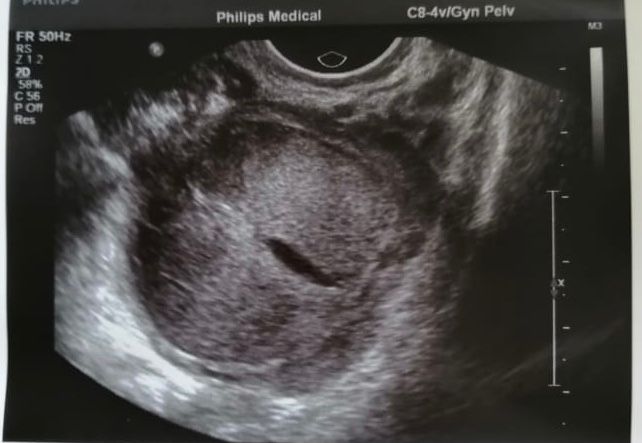

Что за киста ?

Девочки,кто разбирается? Это киста желтого тела или фолликулярная киста? Это киста подруги,которая 4 года не может забеременеть(стимуляцию, лапароскопию) всё сделала, у кого после лапароскопии получилось забеременеть? Через сколько? У неё диагноз спкя,овуляция то бывает,то нет, а остальное всё в порядке,но что-то не получается все равно

и на фото киста фолликулярная или желтого тела? Врач сказала ей фолликулярная,но написала что желтого тела